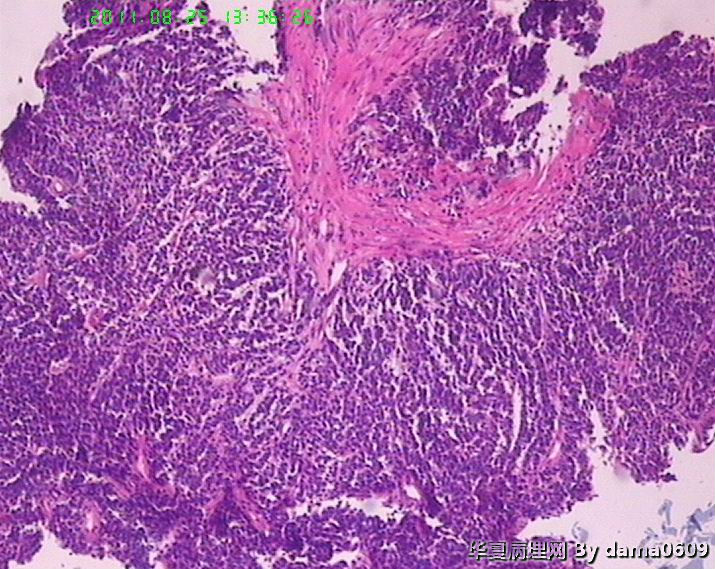

患者男性,39岁。以回盲部肿物行肠镜检查、活检。镜下四块组织内有两块见呈巢状的小细胞(如图

),另两块为粘膜慢性炎表现及坏死组织。学生不知如何分类:未分化癌?类癌?小细胞癌?请老师指教。谢谢!

细胞核较小、深染、一致,核分裂象少见,支持典型类癌。

神经内分泌肿瘤 淋巴瘤 低分化腺癌。。。

楼主是想说“未分化癌”?片子切的比较厚,考虑神经内分泌肿瘤,低分化腺癌待排。